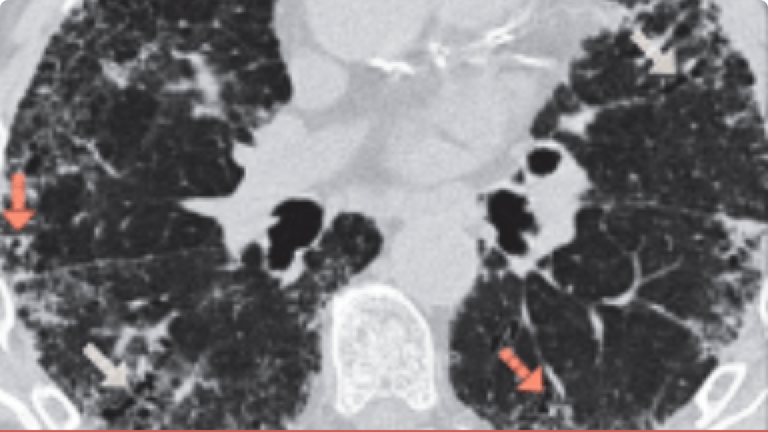

Împreună cu evaluarea clinică, modelele de HRCT toracic și discuțiile multidisciplinare facilitează diagnosticul de primă alegere11

• Discuția în echipa multidisciplinară, care implică contribuțiile expertului radiolog, poate fi necesară pentru a perfecționa în continuare un diagnostic5

• HRCT poate avea un impact semnificativ asupra diagnosticului final, chiar și atunci când un diagnostic histopatologic a fost pus folosind o biopsie pulmonară5

Acest atlas imagistic vă poate sprijini îndiagnosticul PID, ajutându-vă să recunoașteți indicii și caracteristicile cheie ale HRCT și examenului histopatologic.